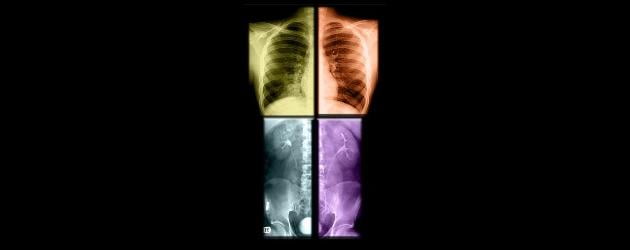

Een goede diagnose stellen is een kunst. Dankzij een geheel nieuwe techniek, die binnen vijf jaar beschikbaar is, komt het stellen van een snelle en pijnloze diagnose binnen handbereik.

Volgens onderzoekers is binnen vijf jaar de techniek beschikbaar om met laserstralen ziektes te diagnosticeren. De diagnose kan dan gesteld worden binnen een paar minuten en is volledig pijnloos.

De laserstralen worden afgeschoten op het weefsel dat wordt onderzocht. Via Ramanspectroscopie wordt de golflengte en intensiteit van de teruggekaatste stralen geanaliseerd. Het voordeel is dat deze techniek sneller en preciezer is dan de huidige methodes en dat deze minimaal invasief is.

De laser heeft een paar minuten nodig om een deel van het lichaam te ‘scannen’. Vervolgens kan in enkele seconden een diagnose worden gesteld. Diagnoses die met Ramanspectroscopie gemaakt kunnen worden zijn botziektes en tandrot.

Een andere voorbeeld  is het traceren van borstkanker. Hierbij is het direct mogelijk om vast te stellen of een tumor goedaardig of kwaadaardig is. Dit voorkomt in veel gevallen een onnodige biopsie, wat alleen al in Engeland 80.000 vrouwen behoedt voor secundaire procedures.